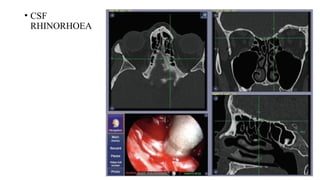

• CSF

RHINORHOEA